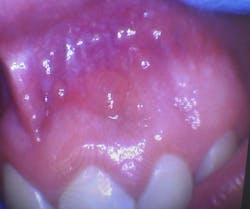

Clinical dental case: Asymptomatic fluid-filled lesions in the vestibular mucosa (nos. 7–10)

Patient presentation: A 17-year-old male patient presented at the initial dental appointment with the following:

Chief complaint: None. The lesions were discovered during a routine oral examination.

Clinical findings:

- Seven asymptomatic, fluid-filled lesions

- Lesions ranged in size from 2 mm to 5 mm

- Lesions similar in color to the surrounding mucosa

- Location: vestibular mucosa, in the region of teeth nos. 7–10

Follow-up appointment: Only three of the original lesions remained.

The presentation of multiple, asymptomatic, fluid-filled lesions on the vestibular mucosa, with a color similar to the surrounding tissue, further supports the likelihood of a mucocele or a mucous retention cyst. The spontaneous resolution of some lesions further strengthens this hypothesis.